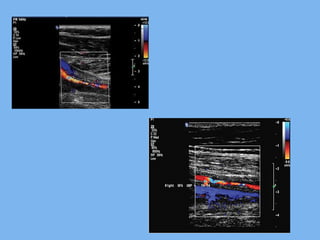

Ultrasound (( ffoorr aacccceessiibbllee aarrtteerriieess..

CDS, CT angiography, MRI and MRA are

able to delineate both the vessel wall

and the lumen. Therefore, they can reveal

vessel wall alterations when the lumen is

still unaffected on angiography